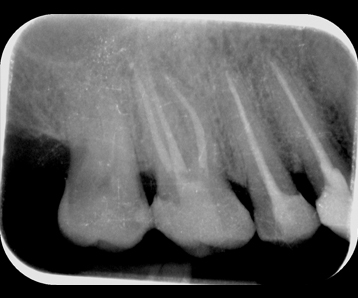

La radiología digital permite obtener imágenes precisas y de alta calidad para el diagnóstico con una baja exposición a la radiación.

Gracias a las radiografías periapicales, las ortopantomografías y las tomografías 3D (CBCT), se pueden planificar tratamientos y realizar diagnósticos más precisos.